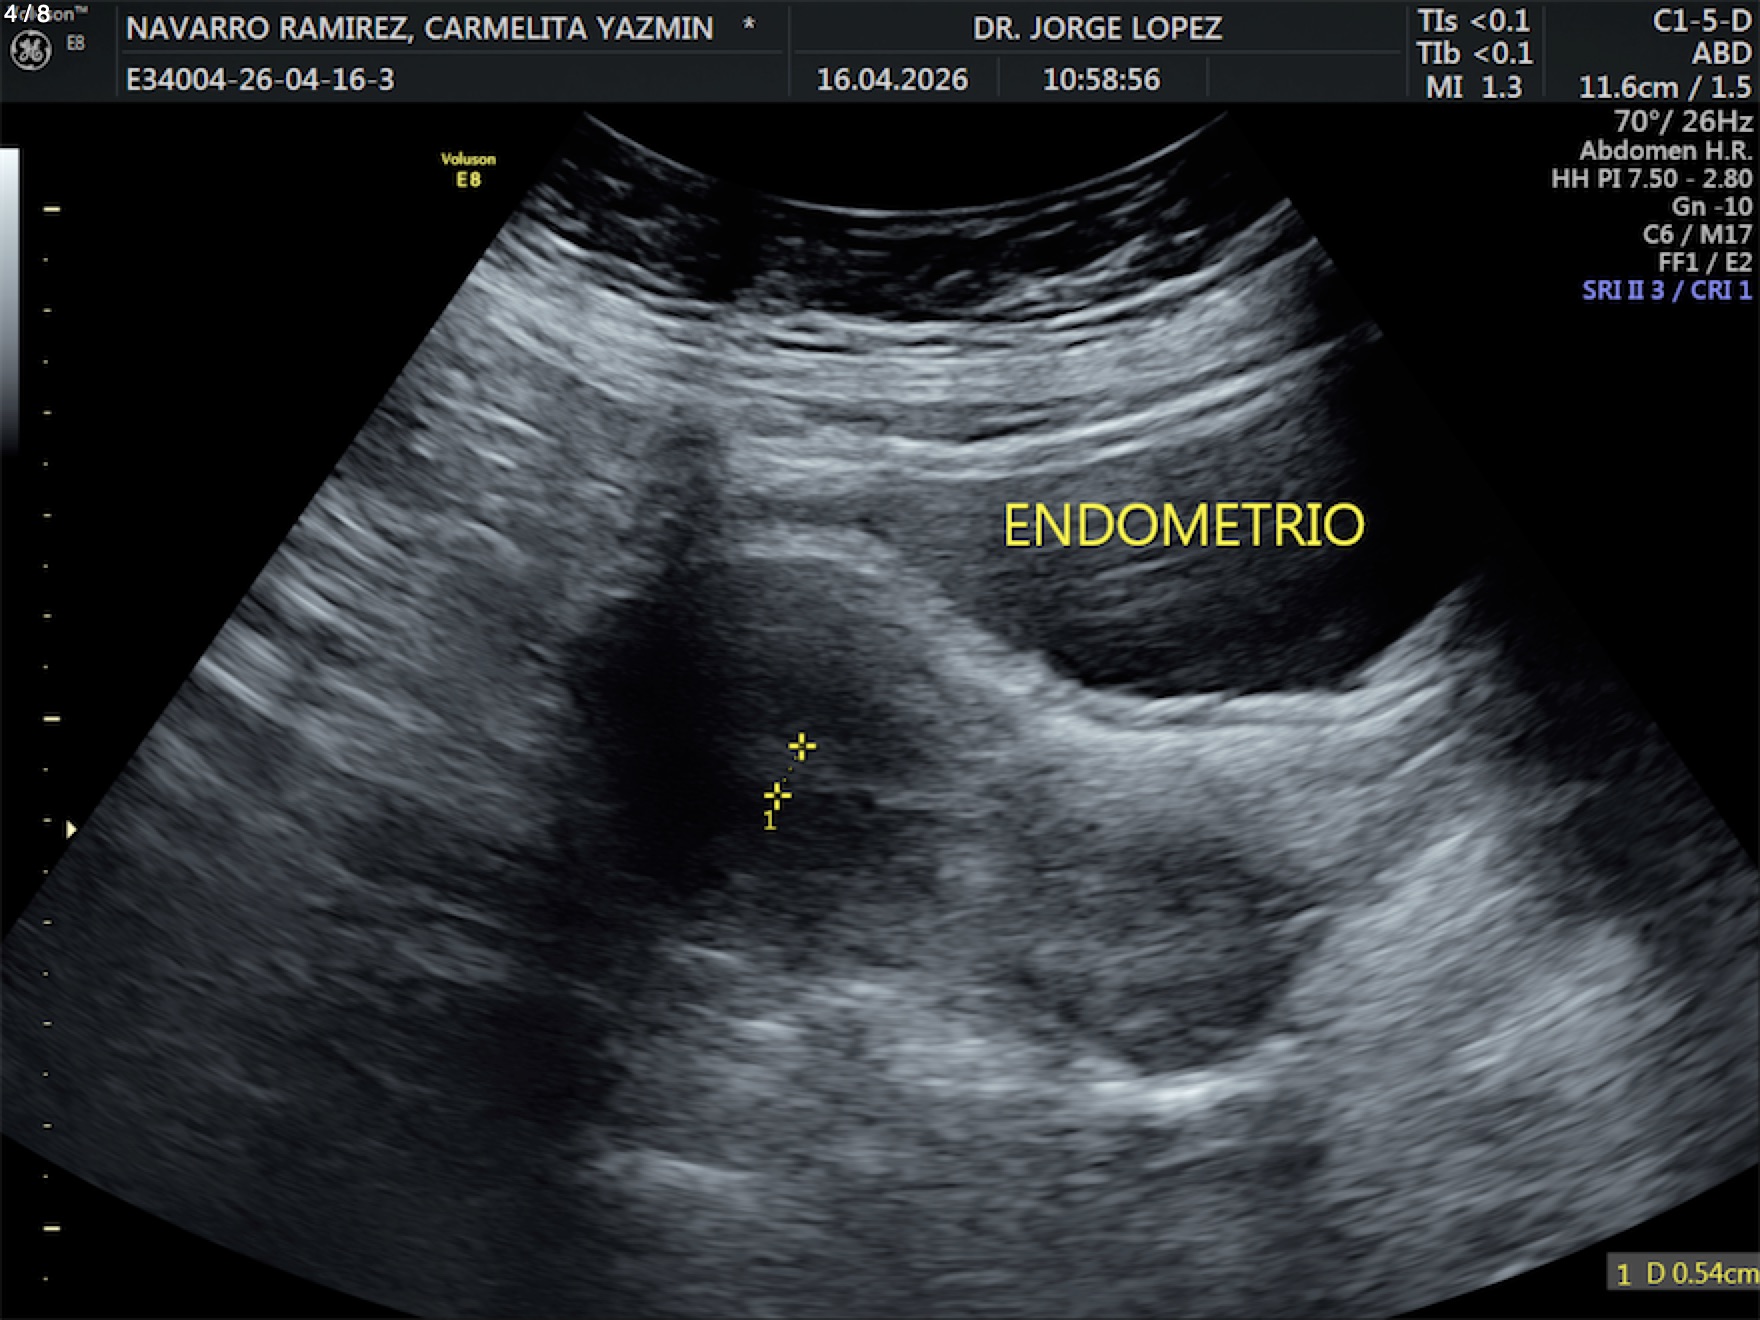

Navarro Ramirez Carmelita Yazmin - Unnamed